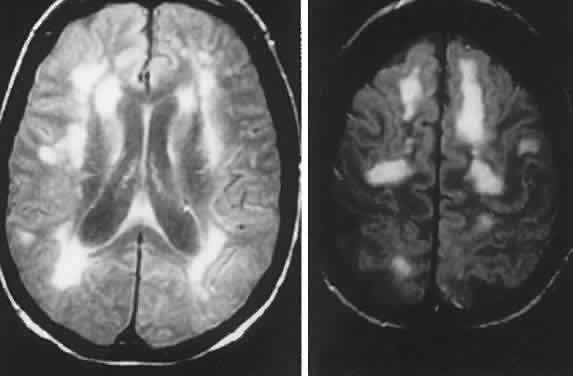

As noted above, Gass1 and others have elaborated a class of acute and subacute, diffuse or focal, presumed inflammatory zonal disorders of the outer retinal layers, now termed AZOOR. Roughly described as “enlarged blind spots” and thus confounding neurologic diagnosis, this somewhat heterogeneous rubric includes MEWDS (multiple evanescent white dot syndrome), multifocal choroiditis, acute macular neuroretinopathy, pseudo-presumed histoplasmosis, and idiopathic blind spot enlargement. These entities share a constellation of signs and symptoms and so raise the question of a spectrum of common origin involving geographic zones of retinal photoreceptors and pigment epithelium. Characteristics include the following: predilection for female patients; acute onset in one or both eyes, associated with photopsias; minimal fundus findings at onset, but eventual minor pigment epithelial disturbances; ERG abnormalities; fluorescein angiographic evidence of geographic thinned pigment epithelium; vitreous cells; and permanent field depressions often close to the physiologic blind spot. Taken as a group, Jacobson and colleagues2 investigated the nature of retinal dysfunction and found patchy but dense scotomas and ERG abnormalities, but no evidence of autoantibodies to specific retinal antigens. Recurrent central nervous system (CNS) inflammation in association with AZOOR is reported,23 characterized by cerebrospinal fluid (CSF) lymphocytosis and multiple magnetic resonance imaging (MRI) signal abnormalities, followed in 6 years by an episode of cervical myelopathy.